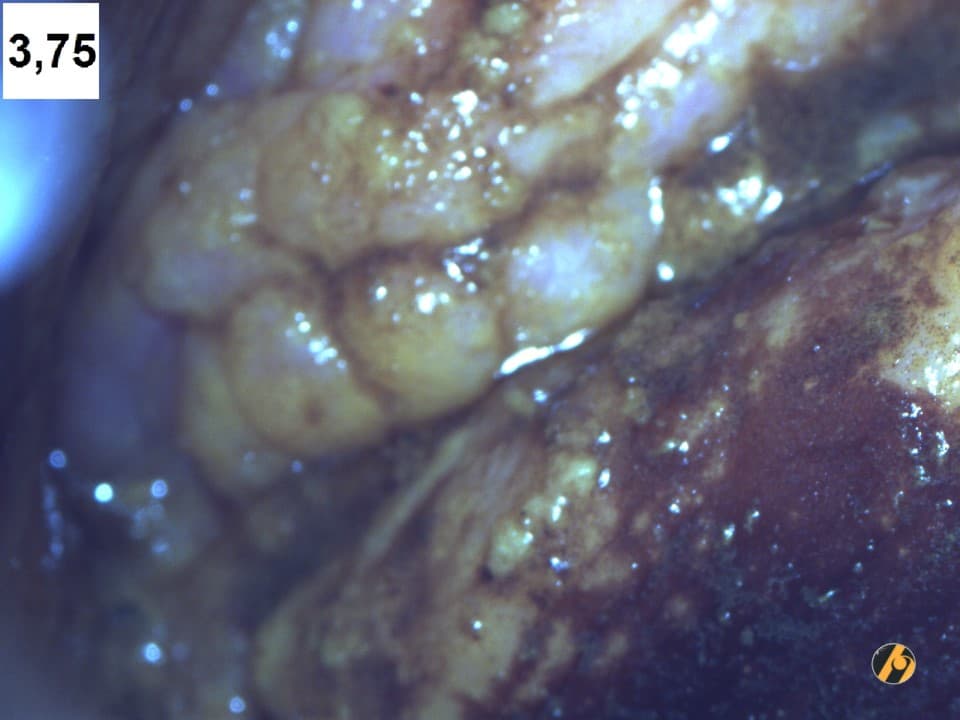

Sumnjive promjene na vagini otkrivaju se prilikom ginekološkog pregleda obično kao crvene ili bijele mrlje: ulkusi (ulcus – vrijed ili ranica) izdignutih rubova ili u ravnini sluznice, ili u obliku bradavičastih promjena. Najčešća lokalizacija ovih promjena je gornja trećina stražnje stijenke vagine. Kod svake sumnjive lezije potrebno je napraviti kolposkopiju, citološki bris, i/ili biopsiju. Kod uzimanja biopsije od pomoći je svakako i Schillerova jodna proba.